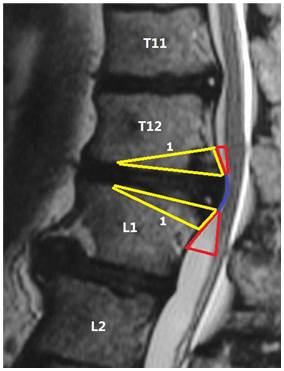

该新术式的另一主要特点是配合应用脊柱经椎弓根内固定、椎体间植骨Cage融合术。其设计理念主要基于以下方面的认识和考虑:首先在长期的临床实践中我们发现胸椎或胸腰段椎间盘突出症患者中大部分合并有病变节段的脊柱局部后凸畸形。我们对一组35例胸椎及胸腰段椎间盘突出症患者的影像学进行了测量分析,结果发现大部分患者存在有不同程度的胸腰段脊柱后凸畸形,其中63%患者后凸畸形角度大于10度,而病变节段的后凸角度大于10度者共15例,占46%。虽然文献中并无对于胸腰段椎间盘突出与脊柱后凸畸形相关的报道,虽然多数学者认为胸腰段椎间盘突出症的发病因素主要系退变所致,但也有许多学者认为外伤及休门氏病也可能引起胸椎及胸腰段椎间盘突出症的发病,该两种疾患均可导致胸腰段脊柱后凸畸形。此外文献中亦可见关于类似问题的相关报道[12,13] 。由此可见虽然休门氏病及后凸与胸椎间盘突出症间的关系尚不明确,但后凸畸形在胸椎间盘突出症患者中确实客观存在。而胸椎固有的生理弯曲即为后凸,且胸椎管面积较小,脊髓无缓冲空间,后凸畸形可致脊髓血运受阻,进一步导致神经功能的恶化。故矫正胸腰段后凸畸形可以加大脊髓缓冲空间,达到间接减压的功效。有实验研究表明后凸畸形的矫正可能有增加脊髓血运的效果,Kawahara等人的研究发现在脊髓轻度短缩的情况下(<10mm)脊髓血运可轻度增加(短缩10mm可增加60%)[14]。而经椎弓根脊柱内固定手术在矫正脊柱后凸畸形的同时也可使脊髓松弛,致血运改善从而有助于患者神经功能的恢复。.

图1b. 经后方极外侧入路手术矢状位示意图,红色区域为“安全三角区”,黄色区域为手术操作切除区域,直线1为楔形截骨线